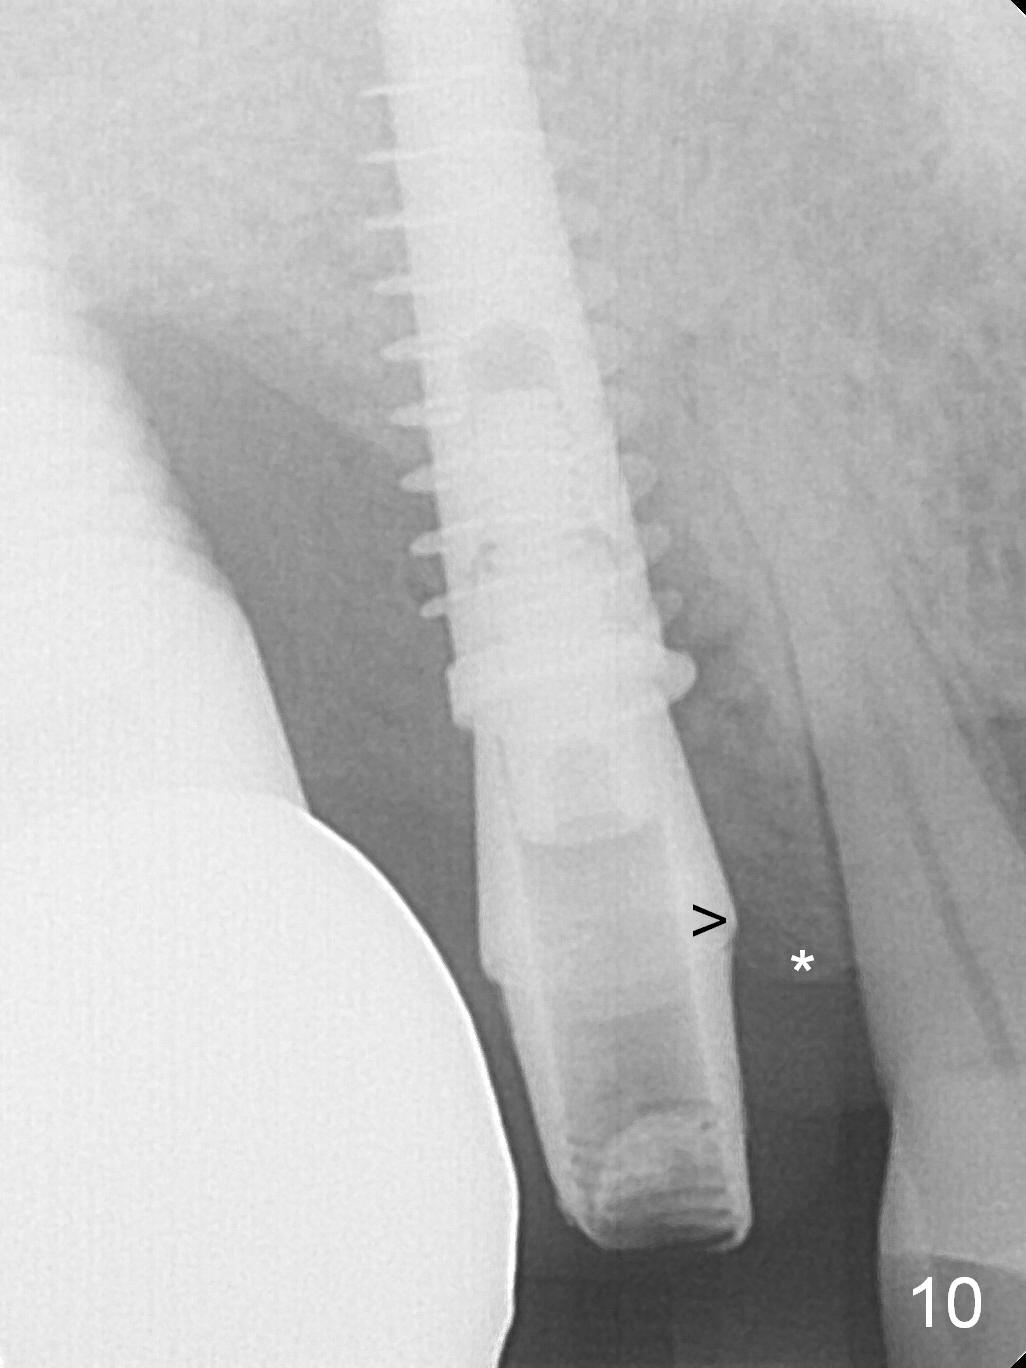

The distal papilla reforms buccally (Fig.8 *) and palatally (Fig.9) 4 months postop. It appears that the 4 mm cuff of the pair abutment (Fig.10 >) is apical to the mesial crest (*). The distal coronal implant threads seem to be covered by bone graft (Fig.11 <). Therefore pair abutments with 5 mm or more cuff are required in cases of the uneven bone. Implants have to be placed deep. CT taken 3 months post cementation (10 months postop) shows that the implant is placed in the middle of the alveolus without apparent thread exposure. CT taken 1 year and 8 months post cementation (Fig.13) shows that the implant is placed in the middle of the alveolus without apparent thread exposure, as compared to those at #2 and 3, which are placed buccal (B).